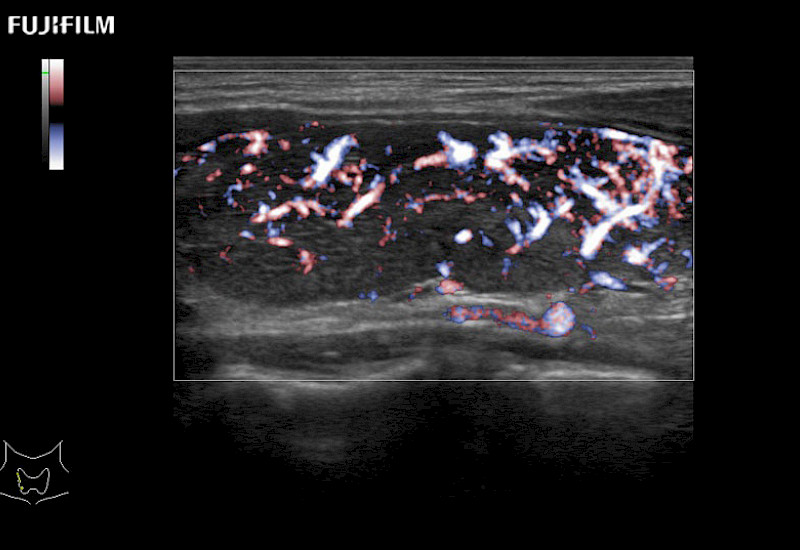

Fujifilm Healthcare understands that Surgical Oncologists demand excellence in their operating rooms — from their staff and the equipment they depend on. Fujifilm Healthcare's dedication to Surgical Oncologists provides outstanding ultrasound technology, professional support and the specialized tools necessary to best perform comprehensive real-time ultrasound imaging.

For precise surgical oncology ultrasound imaging, Fujifilm Healthcare offers premium level solutions that include:

for use during open and laparoscopic procedures: Tumor localization & staging, Ablation, Resection, Biopsy, Transplant, Abdominal exploration, Robotic surgery

Our dedication to Surgical Oncology allows us to offer superior image quality, outstanding system reliability and intuitive use of cutting edge technology.